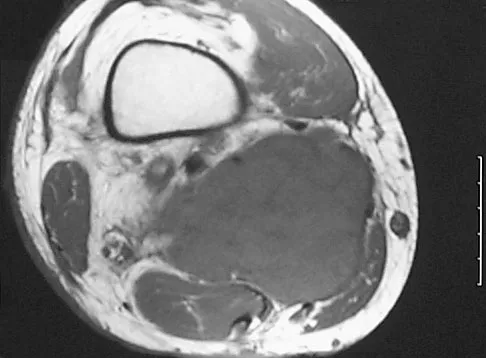

A 14-year-old boy reports progressive right wrist pain. Radiographs are shown in Figure 3a, and a photomicrograph is shown in Figure 3b. What is the most likely diagnosis?